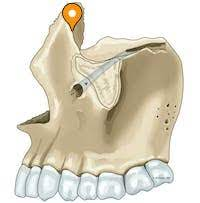

maxilla

maxillary sinus

zygomatic process

alveolar process

alveolus

canine fossa

canine jugum

infraorbital foramen

maxillary tuberosity

lacrimal notch

infraorbital groove

infraorbital canal

anterior lacrimal crest

incisive foramen

incisive canal

premaxilla

palatine torus

maxillary torus

retained incisive (premaxilla) suture

multiple infraorbital foramina

infraorbital suture

abscess

periodontal disease